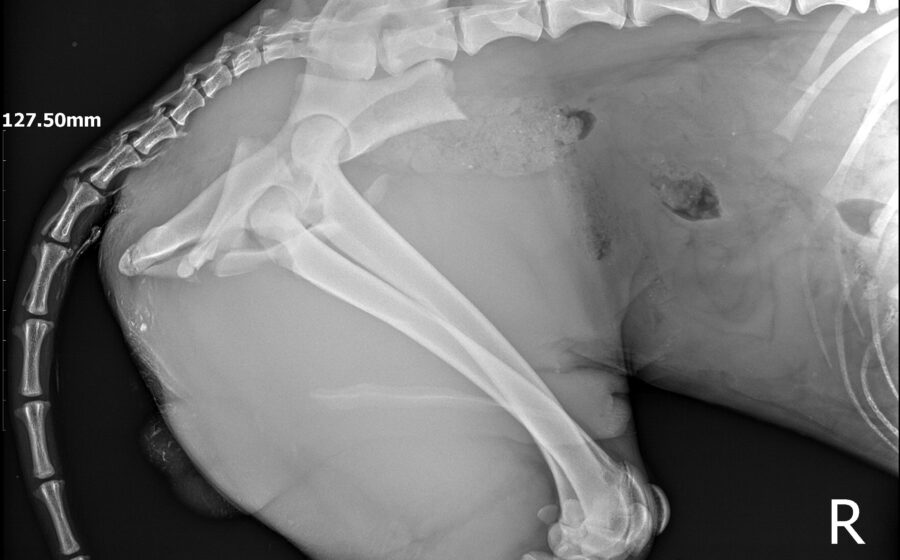

Seine Geschichte ist bewegend: Er wurde schwer verletzt am Straßenrand gefunden. Vermutlich wurde er hinter einem Auto hinterher geschleift und dann liegengelassen. Als Notfall wurde er in die Tierklinik gebracht, wo bei ihm drei Frakturen diagnostiziert wurden – am Darmbein, am Hüftgelenk und am Sitzbeinhöcker. In einer aufwendigen Operation, wurde die Darmbeinfraktur mit einer Platte fixiert. Die Hüftgelenksfraktur wurde nach Einholung zweier deutscher Ärzte-Meinungen nicht operiert, er hat einen Beckenengstand. Mit Physiotherapie wurde er soweit wieder aufgebaut, dass er jetzt mühelos 2 Stunden Spazierengehen kann. Er liebt die Bewegung und flitzt gerne durch den Garten seiner Pflegestelle.